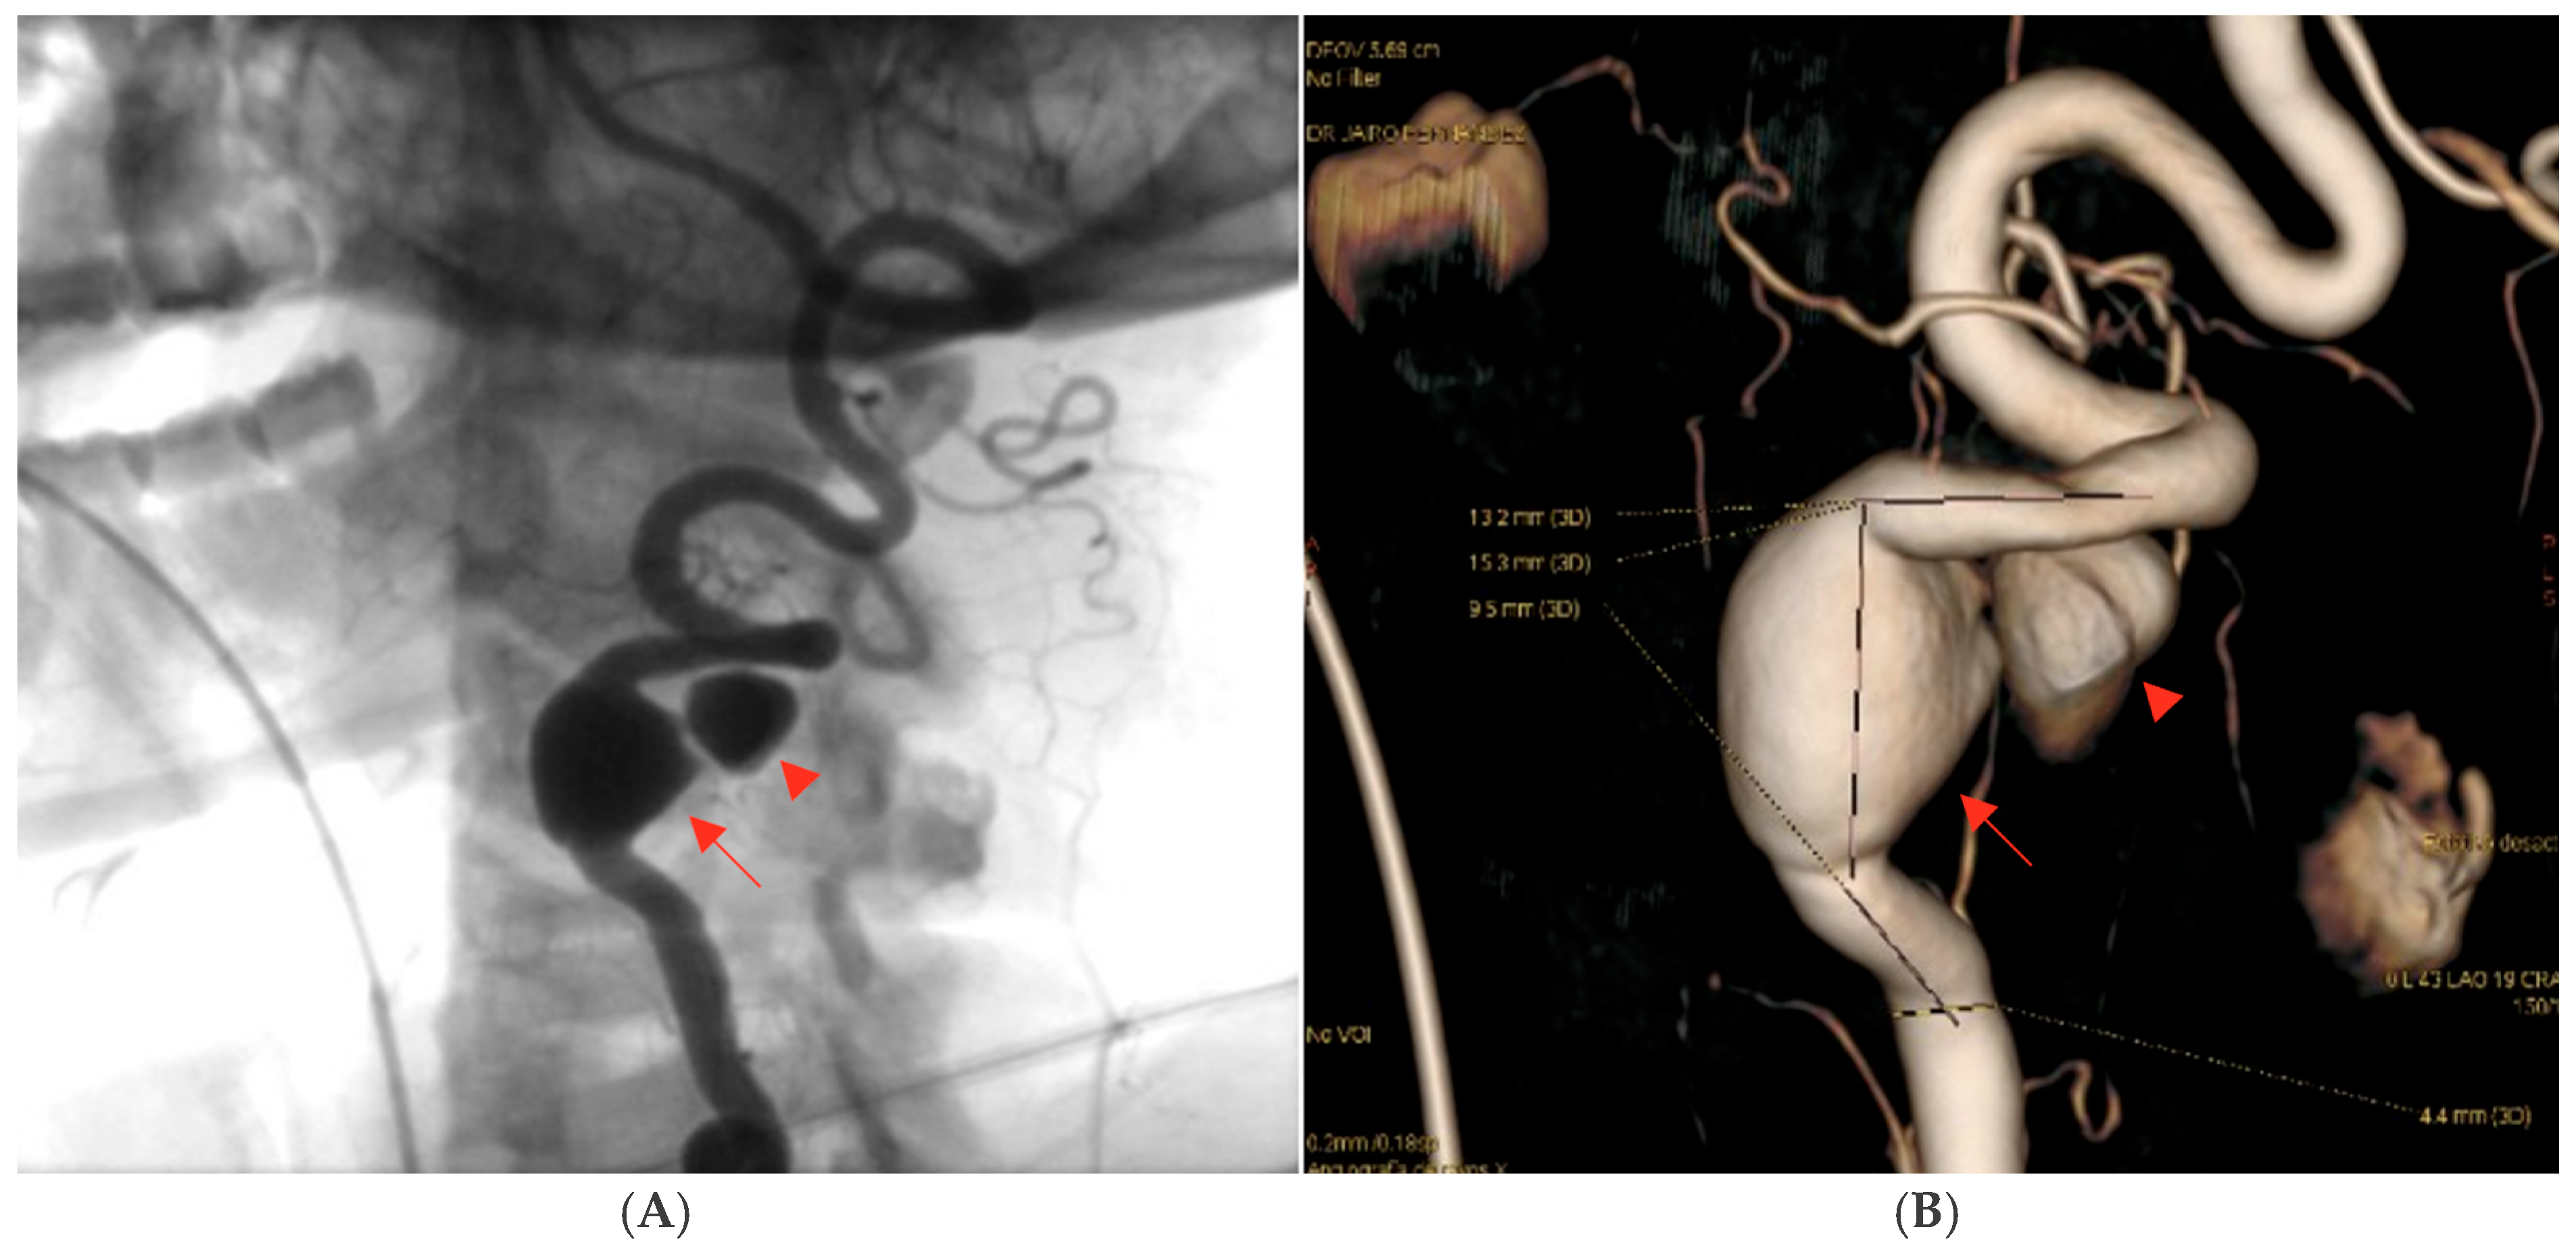

Subsequent computed tomography angiography (CTA) of the neck and cerebral vessels demonstrated a tortuous left vertebral artery with a fusiform aneurysm in the V2 segment measuring 10 × 14 mm, with an associated mural defect and active contrast extravasation into a perivertebral collection of 34 × 24 mm (Figure 2).

Figure 2. Contrast-enhanced CT angiography of the neck and cerebral vessels, axial view (A), sagittal view (B), and coronal view (C), performed after intravenous administration of 100 mL of non-ionic iodinated contrast medium (Iohexol, Omnipaque® 300 mg I/mL, injection rate 3–4 mL/s). Image acquisition was performed during the arterial phase using a bolus-tracking technique (approximately 20–25 s after injection, triggered when the contrast density in the aortic arch reached ≥120 Hounsfield units). The study demonstrates a tortuous left vertebral artery with fusiform aneurysmal dilation of the V2 segment, measuring approximately 10 × 14 mm. A focal mural defect is identified, with active contrast extravasation into a contained perivertebral hypodense collection (34 × 24 mm). The aneurysmal dilation is marked by the red arrow, while the mural defect is indicated by the arrowhead. Source: patient’s medical record, published with prior authorization.